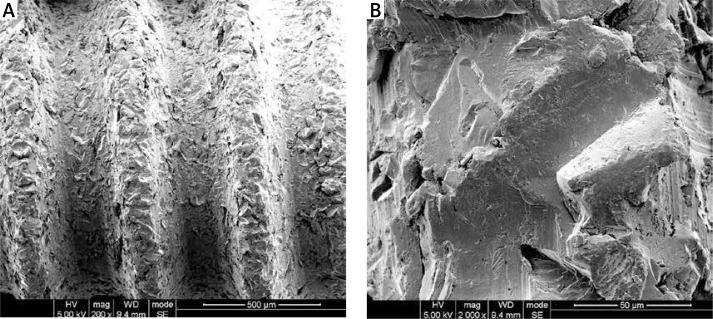

Twelve weeks after bilateral ovariectomy, each rat accepted two titanium screws in the proximal tibiae. All animals were then randomly divided into two groups: the control (10 rats) and OPG group (10 rats). Subcutaneous injection of OPG (10 mg/kg) or vehicle was performed three times a week. Eight weeks later, tibiae with screws were harvested for micro-computed tomography (μCT), histological and biomechanical analysis.

Systemic administration of OPG improved implant osseointegration and fixation in ovariectomized rats, resulting from the increased peri-implant bone mass and improved trabecular microarchitecture.